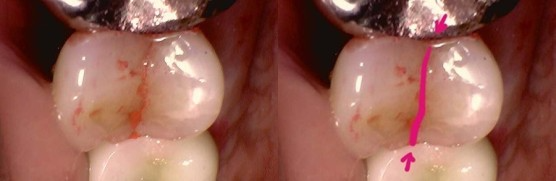

[구강 내부를 직접 살펴보기]

파노라마 사진상으로는 큰 이상이 없어서, 구강내를 다시 봅니다.

큰어금니의 보철치료가 좀 오래되기했으나, 큰 이상은 없어보였습니다.

가만히 보니 큰어금니가 아니라,  작은어금니에 실금이 가있네요.

울산에서 오셔서 당일 바로 신경치료 및 크라운까지 본뜨고 가십니다.